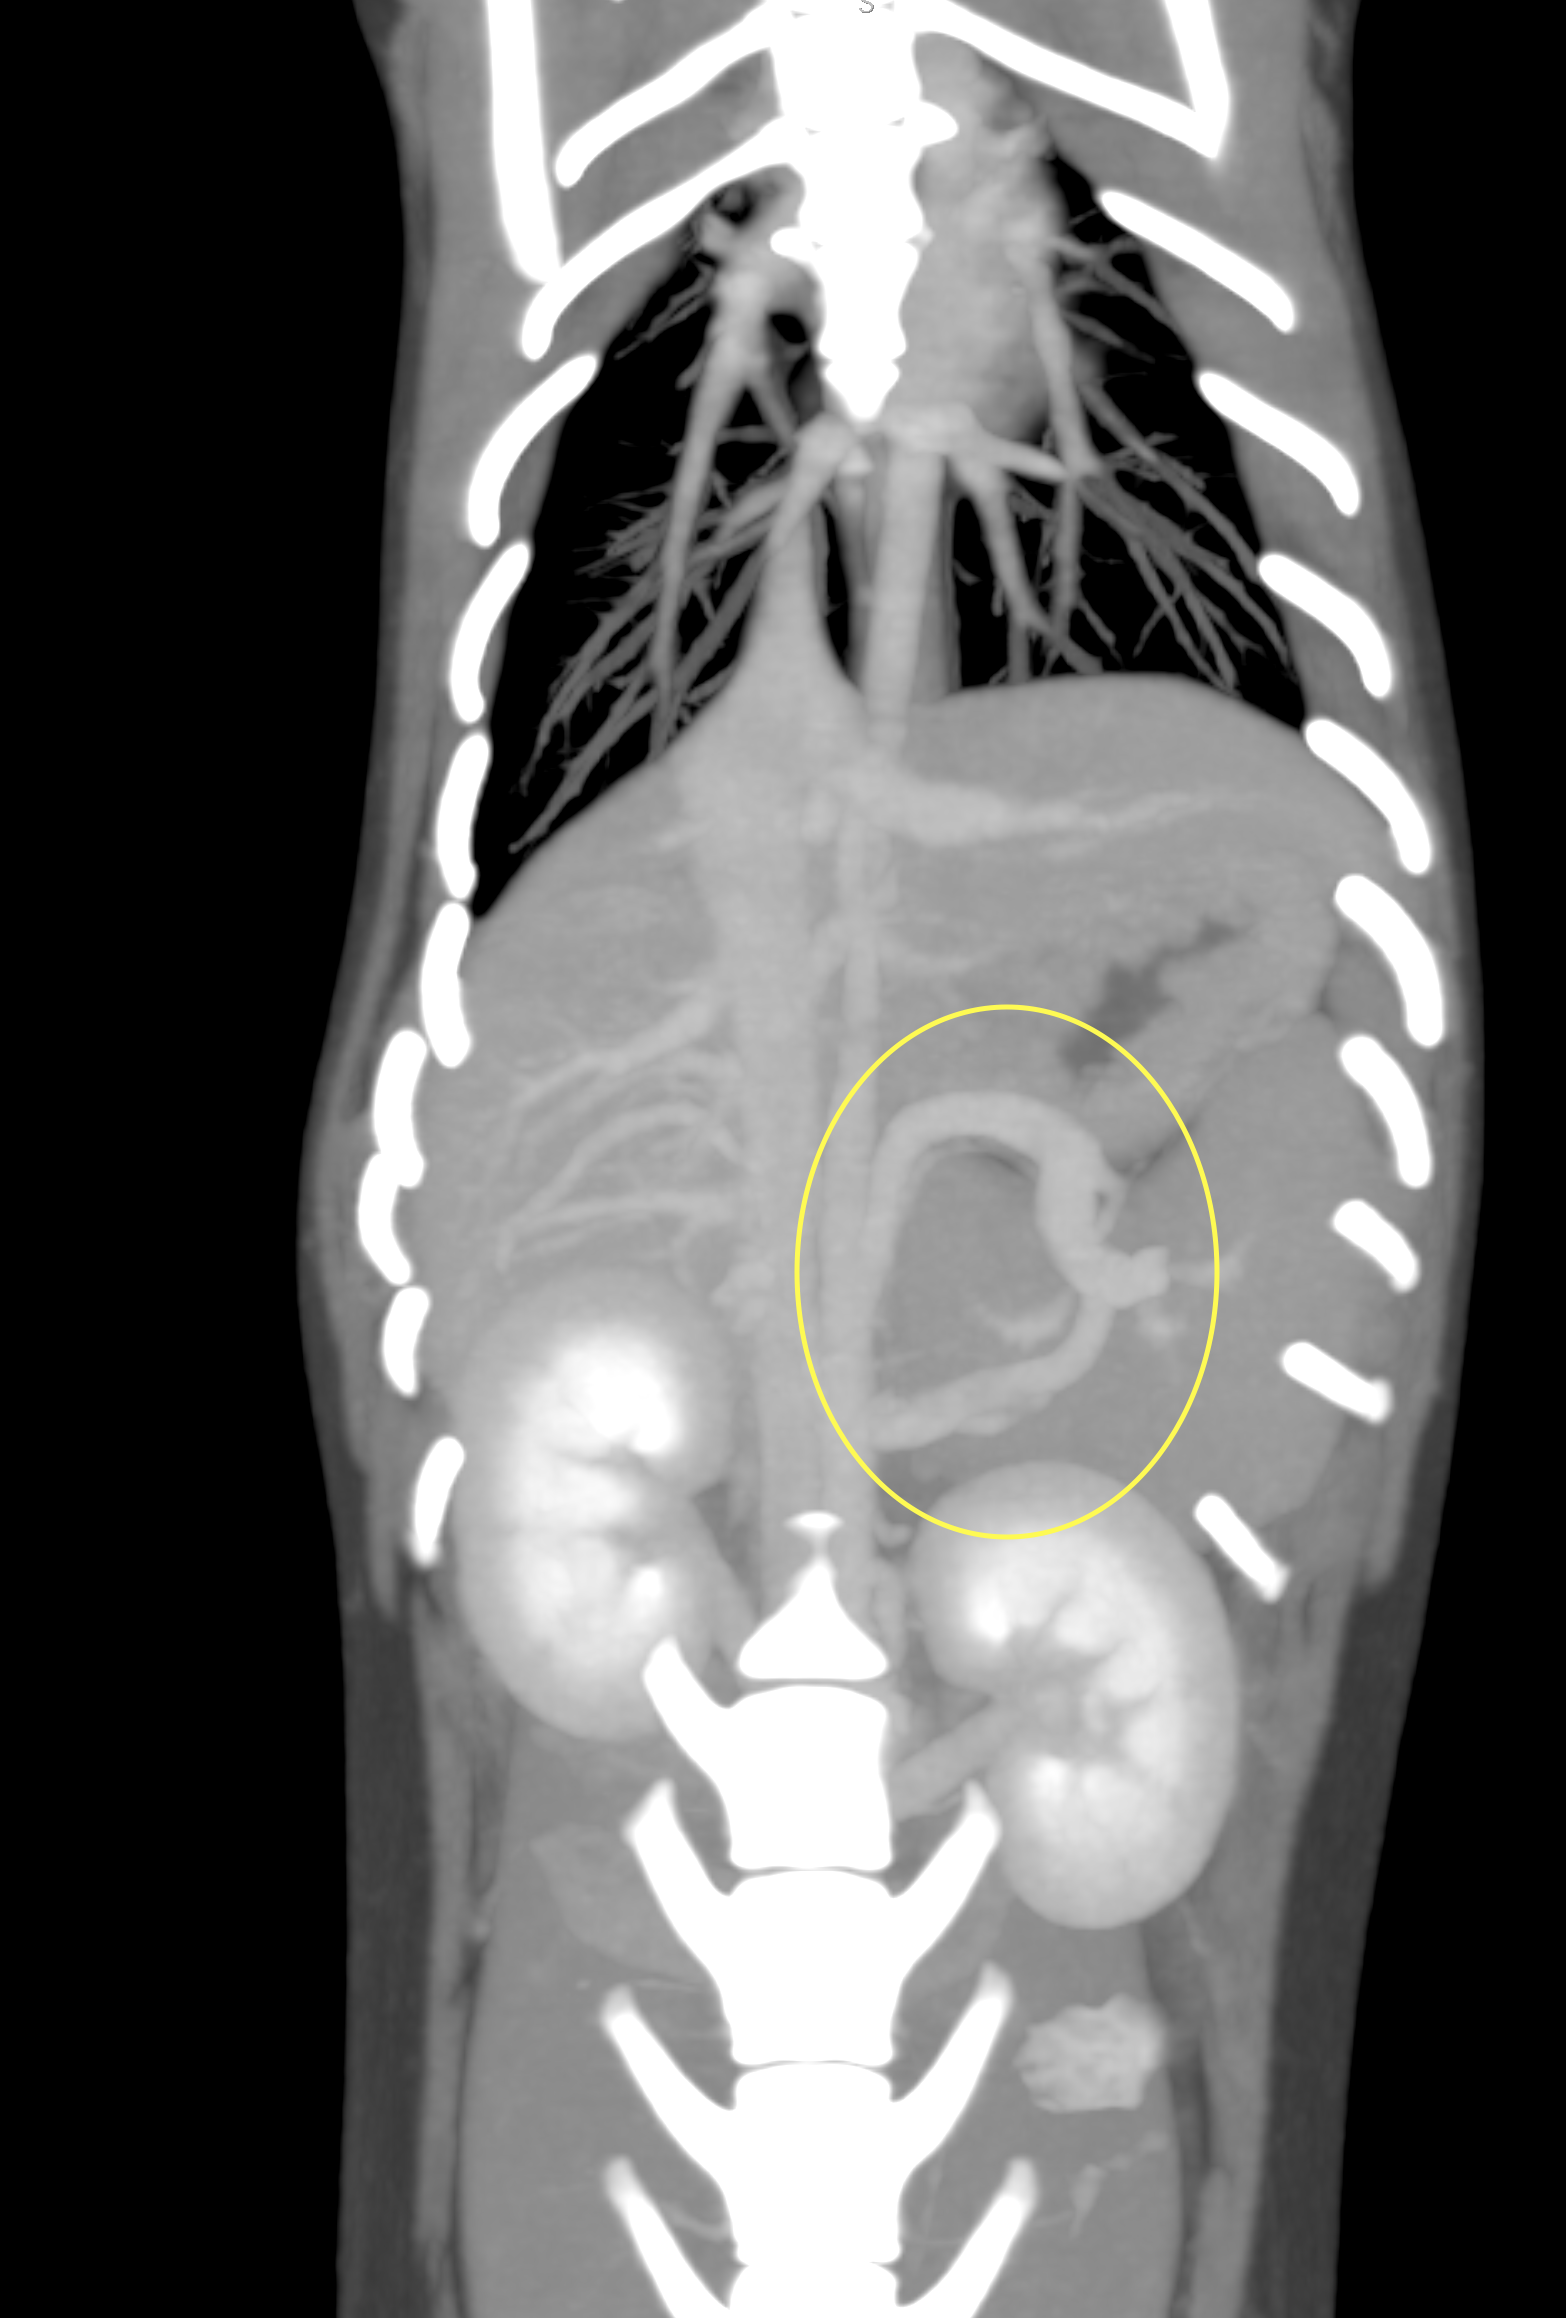

CT画像検査を示します。黄色で示す部分が短絡した異常な血管になります。

CTにおいて、左胃と後大静脈でのシャントが確認できました。

このようにCT画像撮影は、短絡血管の位置を確認するだけでなく手術の計画をたてる上でも非常に重要となります。